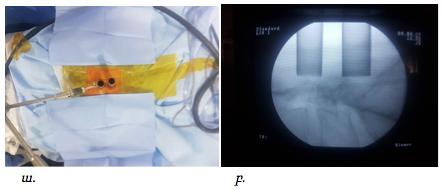

Վիրահատությունները կատարվել են ընդհանուր անզգայացման պայմաններում: Հիվանդի դիրքը փորի վրա էր: Նախքան վիրահատությունը կատարվում էր անհրաժեշտ միջողային աճառի մակարդակի որոշում՝ համաձայն կողմնային պրոեկցիայում կատարված ռենտգեն հետազոտության: Մաշկի գծային կտրվածքըկատարվում էր միջին գծից լատերալ մոտ 1.5-2սմ այնպես, որ համապատասխաներ ելունային հոդի մեդիալ սահմանին, ինչը որոշվում է հսկիչ ռենտգեն հետազոտմամբ առաջահետին պրոեկցիայում:

Վիրահատական մուտքի պլանավորումը ցույց է տրված նկար 1 և 2-ում:

Նկ. 1 Ներվիրահատական լուսանկար: Պատկերված է L4-L5 միջողային մակարդակի վիրահատման համար գծային կտրվածքը՝ մոտ 1.5սմ երկարությամբ (ցույց է տրված սլաքով)

Նկ. 2 Ներվիրահատական ռենտգեն նկար՝ վիրահատական մուտքի պլանավորում

ա. Կողմնային պրոեկցիայում ասեղը տեղադրված է L4-L5 մակարդակին:

բ. Առաջահետին պրոեկցիա՝ ասեղի ծայրը գտնվում է ելունային հոդի միջային եզրին